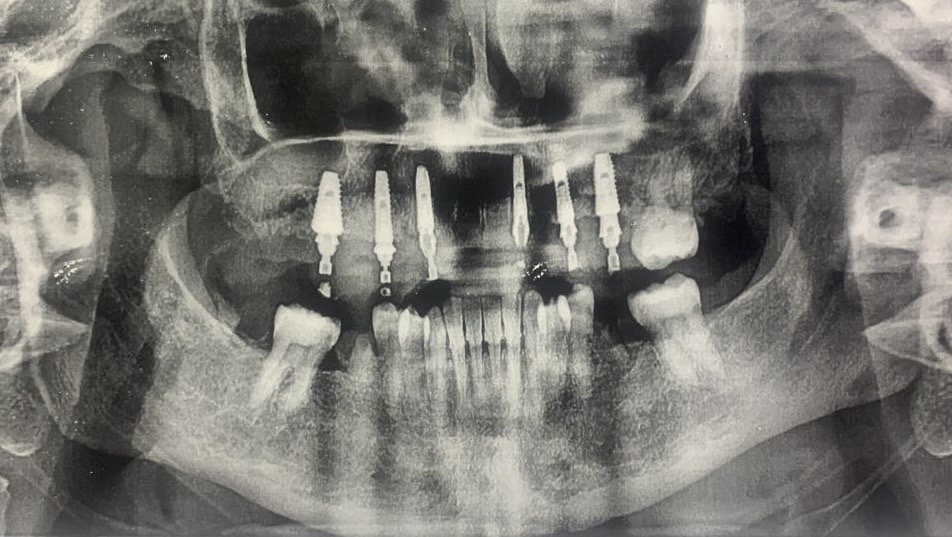

The female patient had been suffering from tooth loss for several years, particularly in the maxillary arch, where almost no functional teeth remained. This condition resulted in compromised masticatory efficiency and impaired speech articulation, the panoramic radiograph was taken before the treatment.

Fig. 2: The panoramic radiograph before treatment